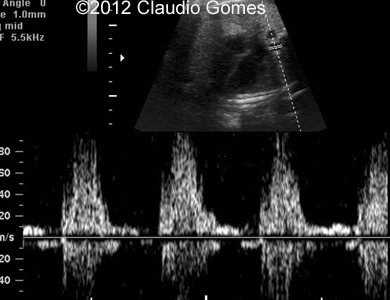

Images 8-11: Persistent right umbilical vein and Inferior vena cava interruption with continuity of the flow via Azygos vein on grayscale and color Doppler

Fig8

Fig9

Fig10

Fig11